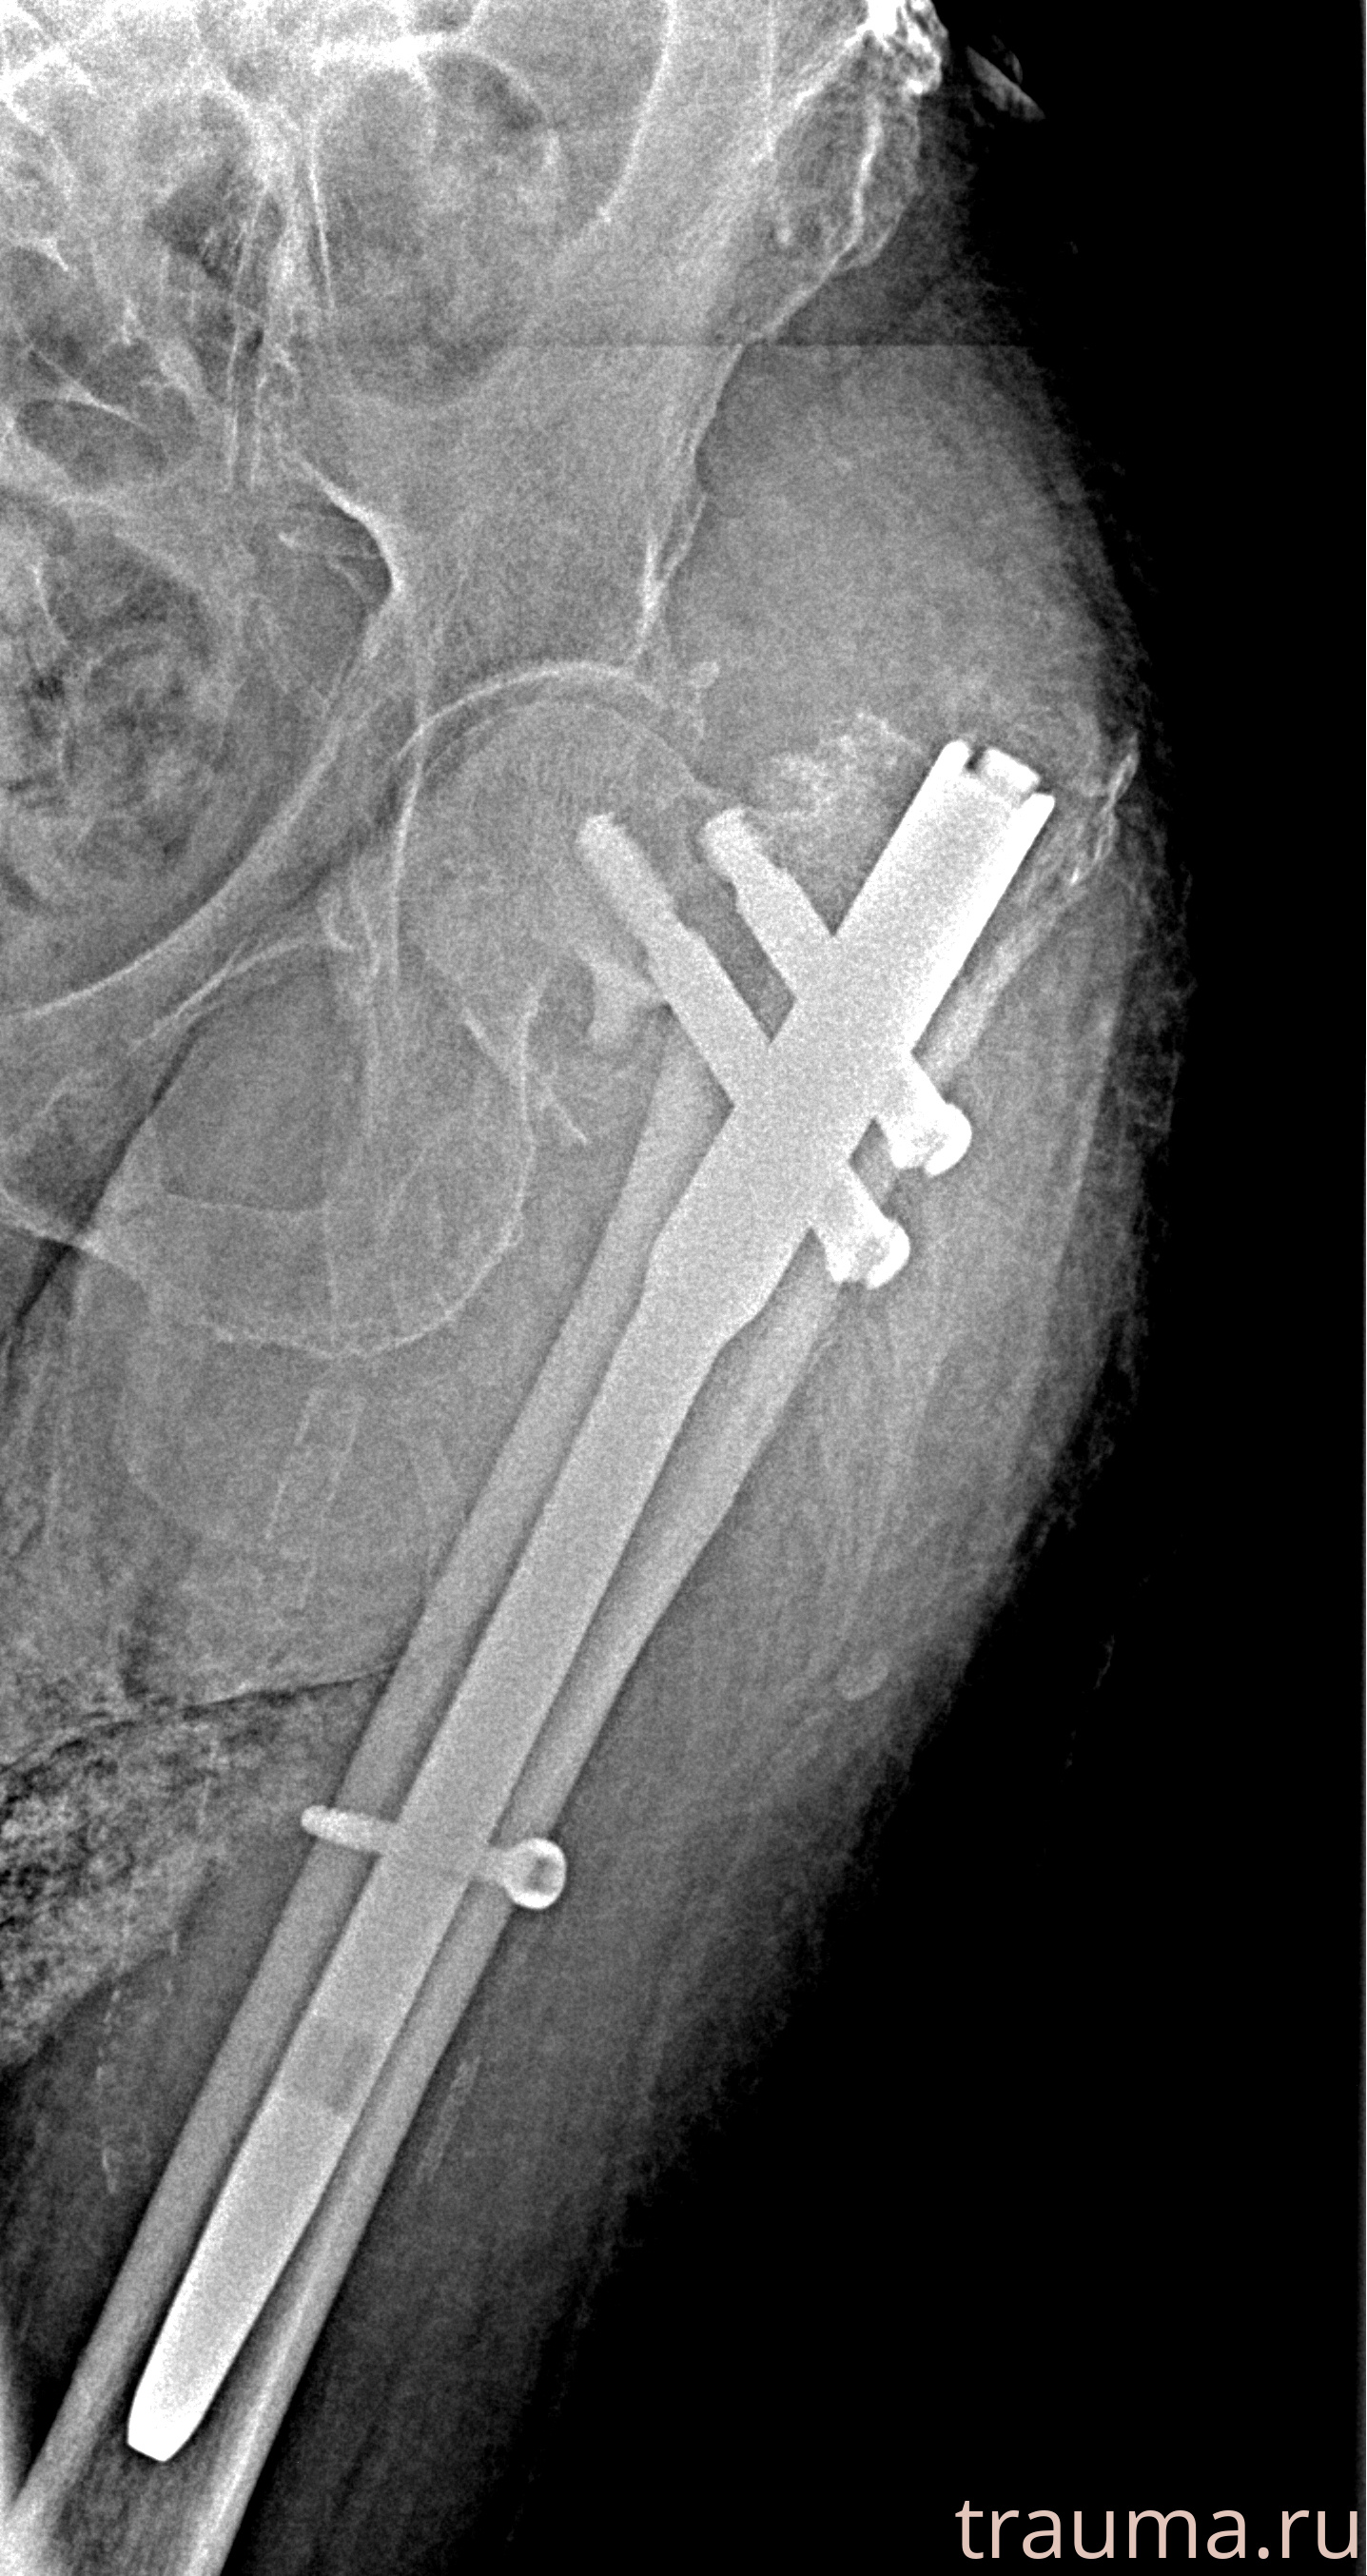

Рентгенограммы

Рентген на дому: по вашему адресу приезжает врач-рентгенолог, травматолог-ортопед с мобильным рентгеновским аппаратом, проводит диагностику травмы или заболевания, делает необходимые рентгенограммы, дает рекомендации по дальнейшему лечению. Получить качественные снимки в домашних условиях возможно благодаря уникальной методике, разработанной МосРентген Центром для института  Склифосовского

при переломе шейки бедра и пневмонии от компании МосРентген Центр - партнера Института имени Склифосовского